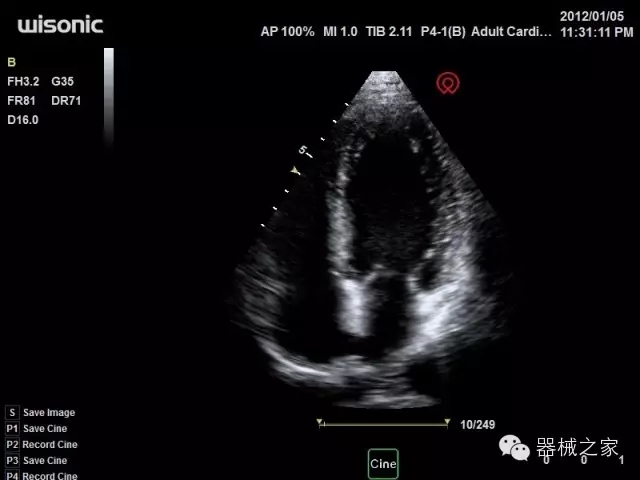

經(jīng)典產(chǎn)品:四葉草

臨床圖片賞析

產(chǎn)品特點(diǎn)